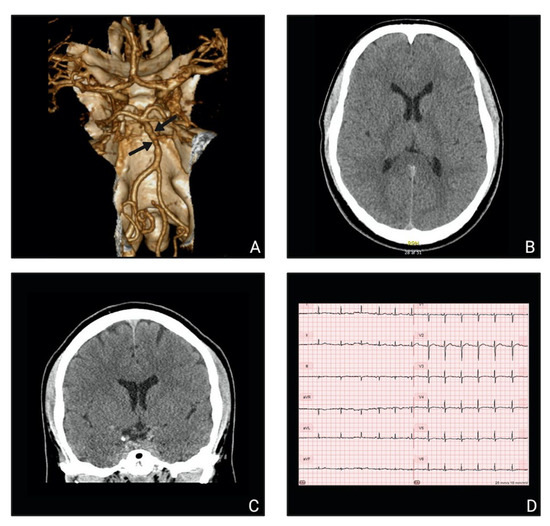

2. Case Presentation